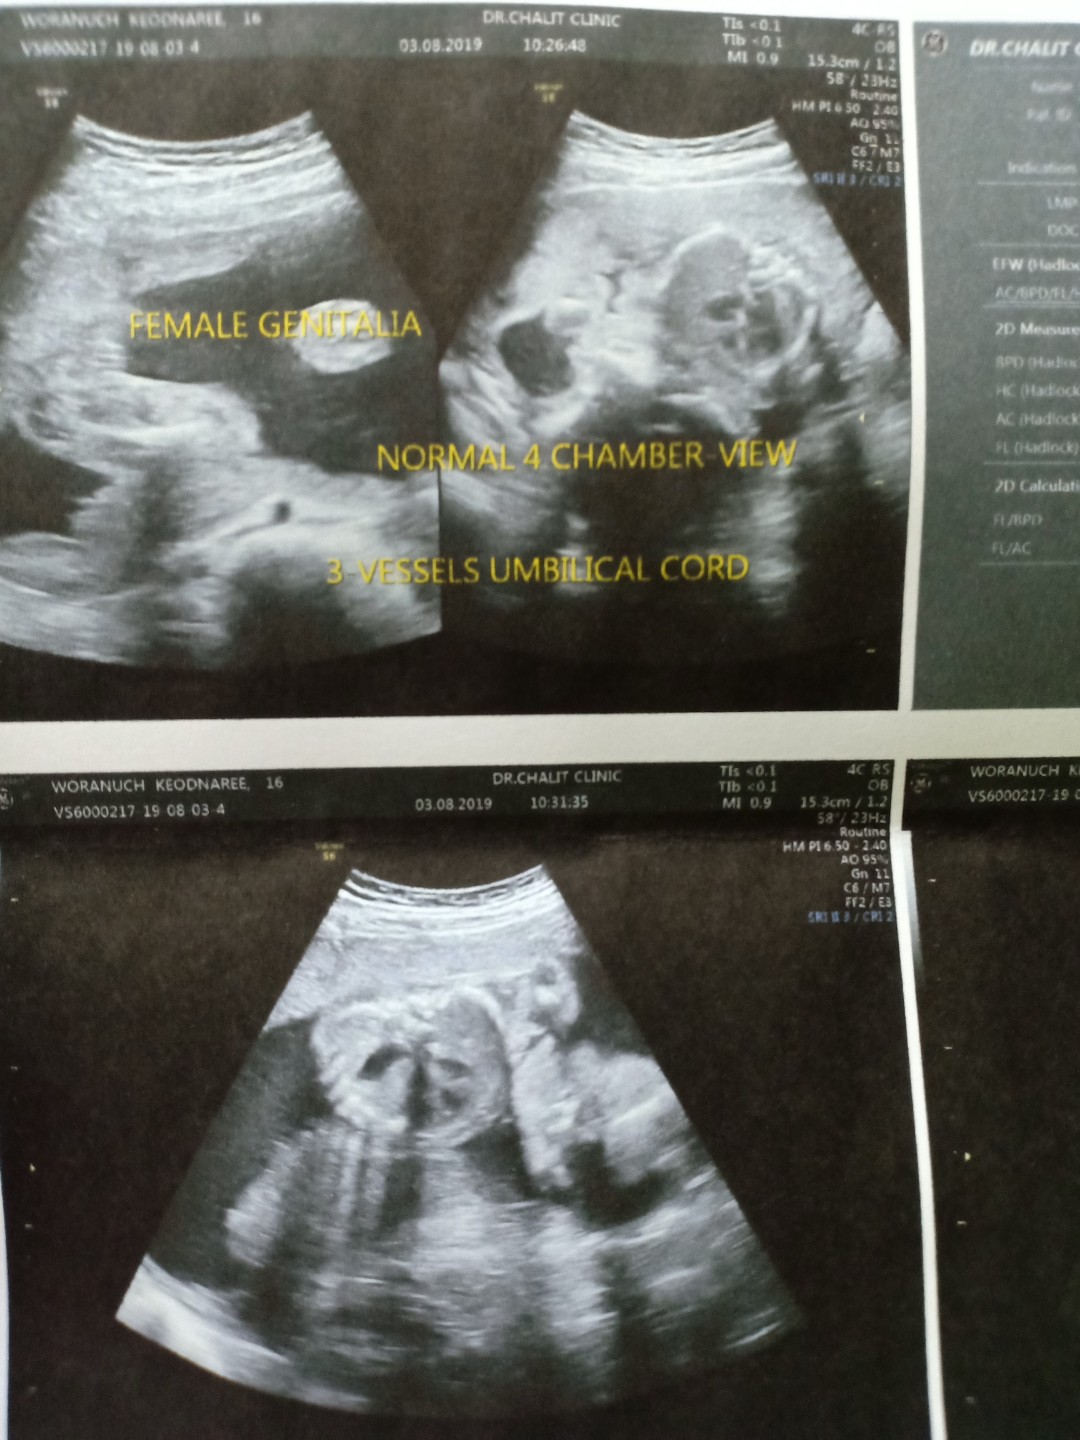

25w ผญ จ้า 3D